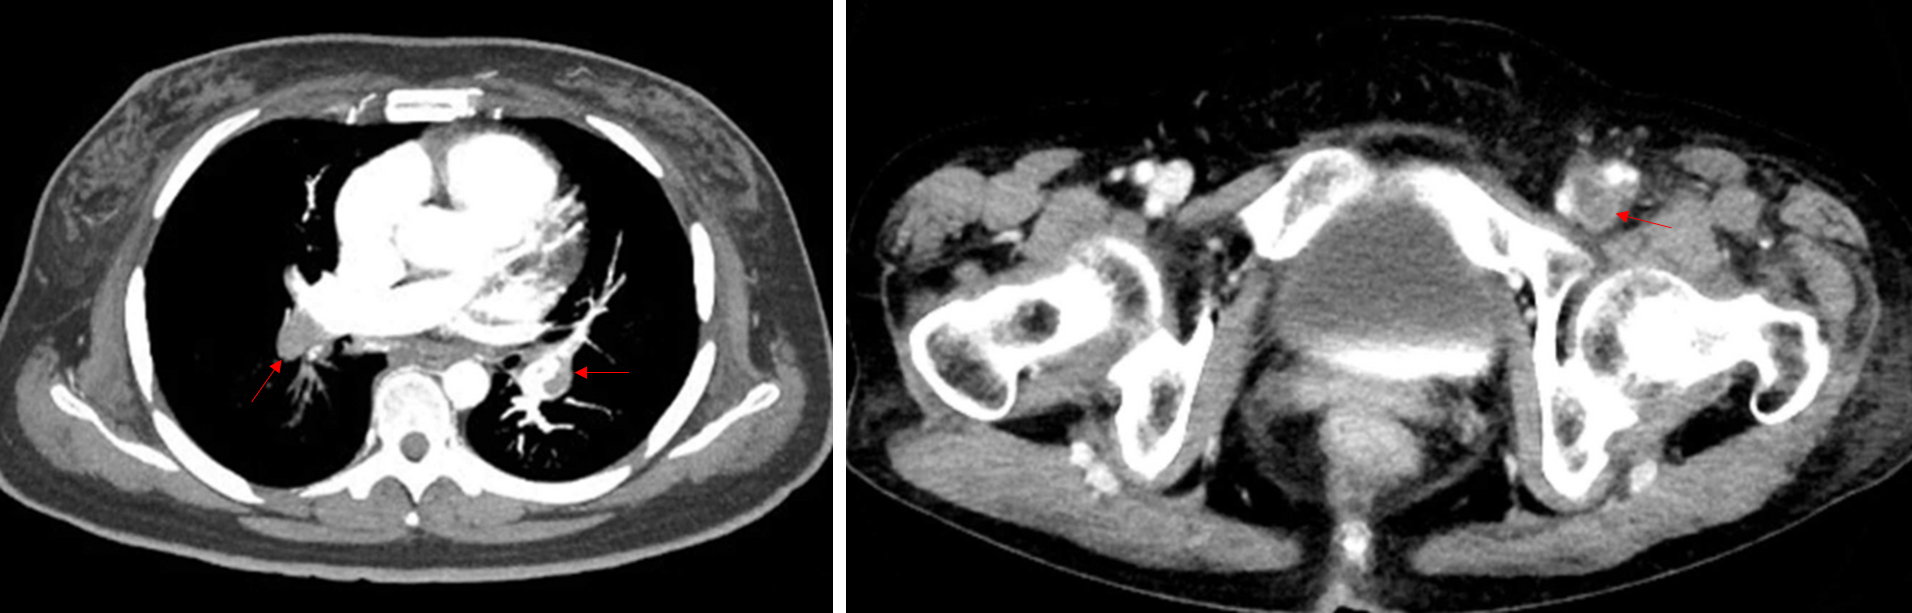

64세 남자가 1일 전부터 숨이 찬다며 병원에 왔다. 10일 전 발생한 뇌출혈로 치료를 받은 후 퇴원하였다. 20갑·년의 과거 흡연자이다. 혈압 146/86 mmHg, 맥박 94회/분, 호흡 24회/분, 체온 36.4℃이다. 가슴청진에서 심음과 호흡음은 정상으로 들린다. 가슴 컴퓨터단층촬영 사진과 하지 컴퓨터단층촬영 정맥조영사진이다. 혈액검사 결과는 다음과 같다. 치료는?

Img | Chest CT: PTE in both main lobar pulmonary arteries Lower extremity CT angiography: DVT in Lt. external iliac vein |

• CT상 Rt. main pulmonary artery 및 Lt. lobar pulmonary artery에 thrombus가 확인되므로 PTE로 진단하며, Lt. external iliac vein에 thrombus가 확인되므로 DVT로 진단한다. 10일 전 뇌출혈로 인해 입원치료 중 시행한 bed rest로 인해 DVT가 발생하였으며, DVT가 embolism되어 PTE로 발전한 것으로 추정된다.